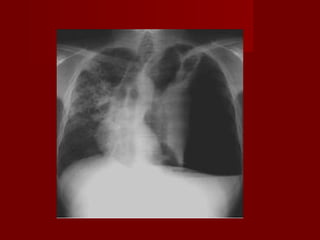

RADIOLOGIARADIOLOGIA

VALOR LIMITADO PARA DXVALOR LIMITADO PARA DX

UTIL PARA DESCARTARUTIL PARA DESCARTAR

OTRASOTRAS..